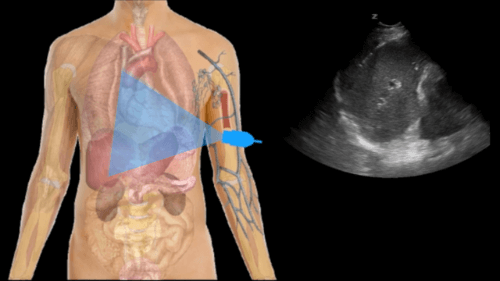

The Focused Assessment with Sonography in Trauma (FAST) has become an integral part of a trauma survey, and is performed immediately after the primary survey of the ATLS protocol…

Additionally, the Extended FAST Exam (EFAST) will detect hemopericardium, hemothorax, & pneumothorax.

Many trauma patients have internal injuries that are not apparent on physical exam. A properly performed EFAST identifies significant bleeding into the peritoneal, pleural, or pericardial spaces and expedite a potentially life-saving intervention.

- A clear & concise method for performing the 4 classic FAST windows (RUQ, LUQ, Pelvic, & Cardiac)

- Cardiac Window